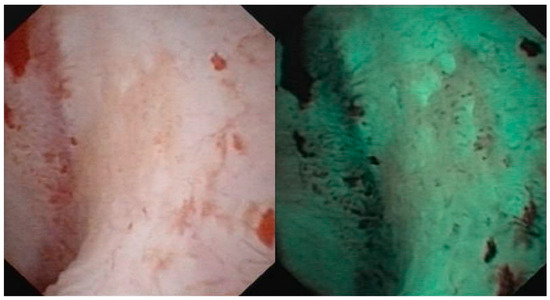

- Iordache, V.F.; Geavlete, P.A.; Georgescu, D.A.; Ene, C.V.; Păunescu, M.A.; Niculae, A.; Peride, I.; Neagu, T.P.; Bulai, C.A.; Bălan, G.X.; et al. NBI-assisted digital flexible ureteroscopy in transitional renal cell carcinoma—An evidence-based assessment “through the looking glass” of the pathological analysis. Rom. J. Morphol. Embryol. 2018, 59, 1091–1096. [Google Scholar] [PubMed]

- Meyer, F.; Al Qahtani, S.; Gil-Diez de Medina, S.; Geavlete, B.; Thomas, A.; Traxer, O. Narrow band imaging: Description of the technique and initial experience with upper urinary tract carcinomas. Prog. Urol. 2011, 21, 527–533. [Google Scholar] [CrossRef]